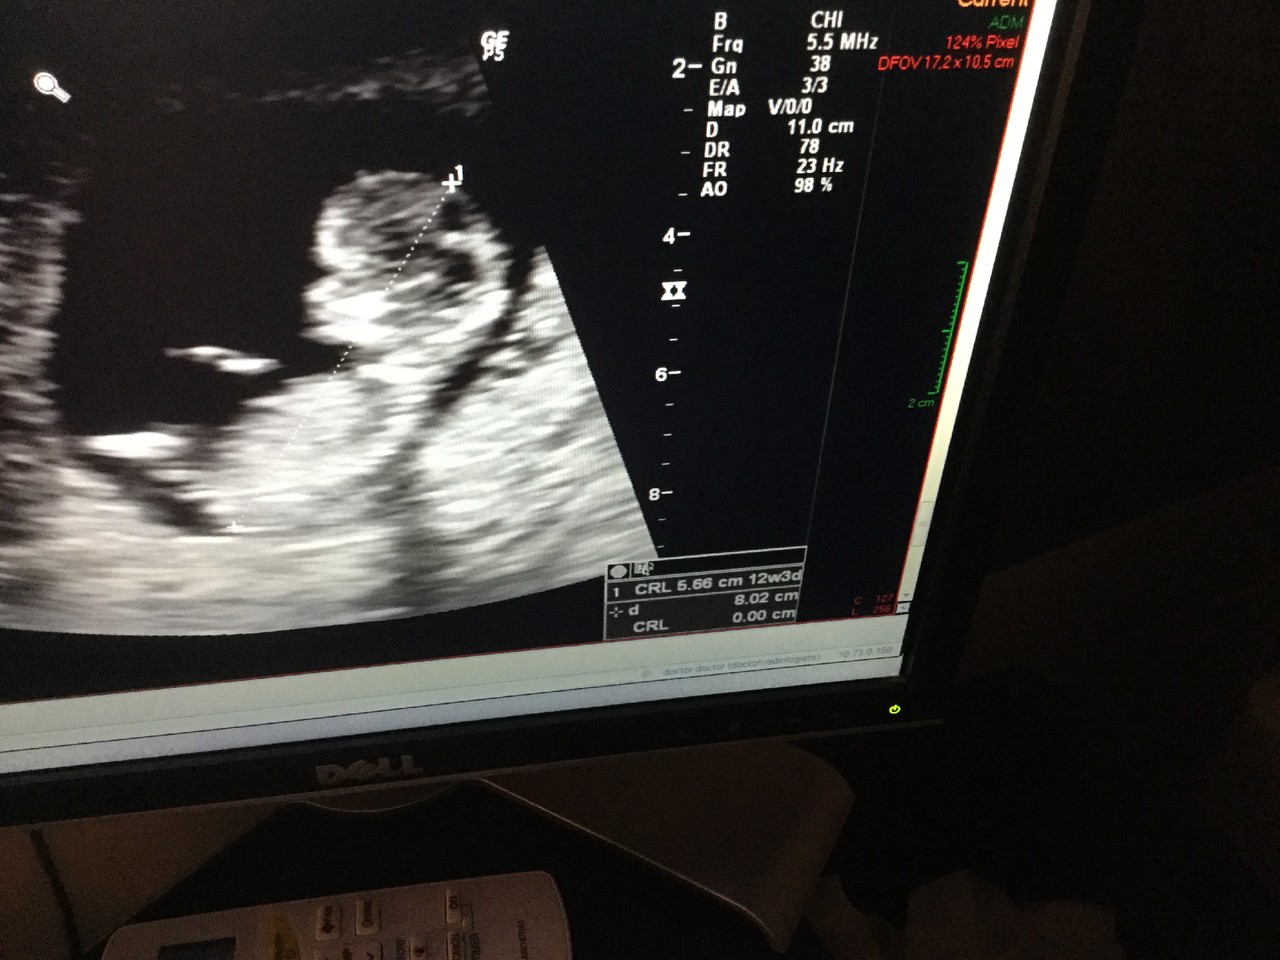

Um dia, o impossível aconteceu. Um dia, descobriu que estava grávida do filho impossivel.

Chora ao ouvir o coração do filho impossivel. Do "acidente" impossivel, aos 40 anos, depois de um diagnóstico de infertilidade, de um cancro da mama e de uma depressão. Chora e ri ao mesmo tempo. E diz que mesmo que o pai não o queira, ela vai fazer tudo por este milagre.